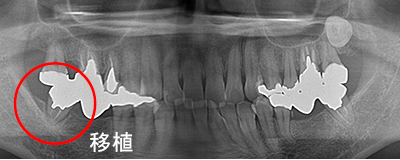

Before

After

左上の親知らずの歯を移植しました。20代前半の症例です。

ご自身の歯のため親和性が高く、移植後も不自由なく機能しています。